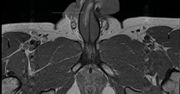

Informacja ta z pewnością przerazi niejednego mężczyznę. Warto jednak na samym początku dodać, że przydarza się bardzo, bardzo rzadko. Mężczyzna z USA opowiedział niedawno w podcaście "How To Do It" o swoim smutny przypadku. Po przechorowaniu COVID-19 stracił 1,5 cala długości przyrodzenia. Chorował na zespół ED, po którym na stałe doznał uszkodzenia ciał jamistych. To jeden z pierwszych tak medialnych przypadków.